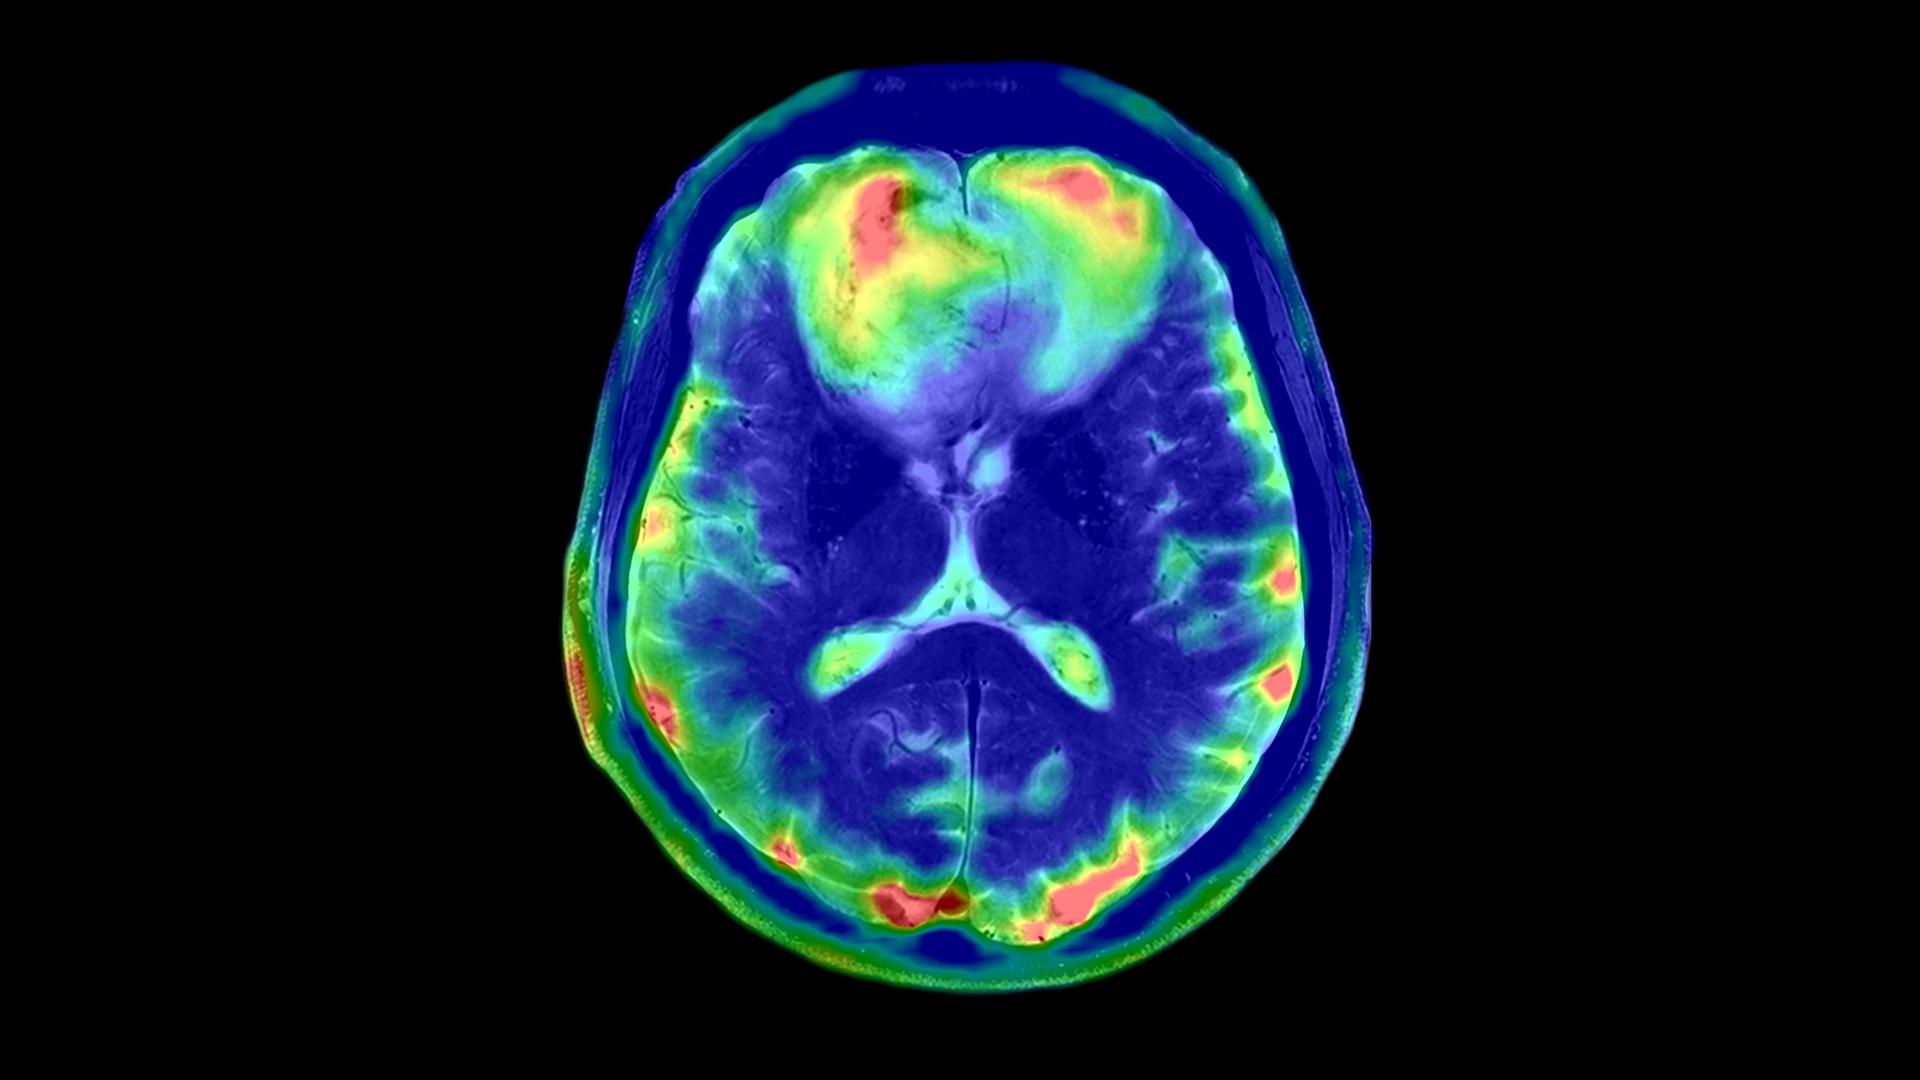

Enhanced Gradient Strength for Unprecedented Precision

With a remarkable gradient strength of 130 mT/m and a slew rate of 250 T/m/s, the MAGNETOM Terra.X takes imaging precision to unprecedented levels compared to conventional systems equipped with 80 mT/m gradients. This enhanced gradient strength facilitates faster and more detailed imaging, allowing us to push the boundaries of what is possible in research and clinical diagnostics. A huge boost for functional, diffusion and structural MRI capabilities.

Revolutionary Ultra IQ Technology and Deep Resolve

The Siemens Healthineers MAGNETOM Terra.X is equipped with Ultra IQ Technology, including dynamic pTx, unlocking the full potential of 7T MRI. This revolutionary technology, coupled with Deep Resolve, leads to previously unheard resolution and acquisition speed. Researchers at Campus Biotech can now delve deeper into the intricacies of biological structures, paving the way for groundbreaking discoveries and advancements in medical knowledge.